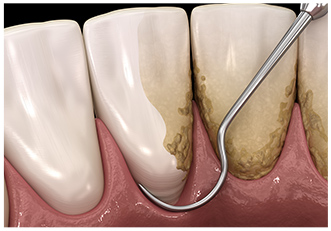

スケーラーという器具を使用し、歯面に沈着したプラークや歯石などを除去します。

特殊な器具を使用してスケーリングでは取り除けない歯周ポケット内部や歯根に付着している歯垢や歯石の除去を行います。

歯周病の進行度に合わせてスケーリングやルートプレーニングなどの治療方法で歯垢や歯石を取り除きます。症状が進行し、重度歯周病と判断された場合は外科治療を行うこともあります。

「スケーラー」という専用の器具を使用して歯に付着した歯石を除去します。